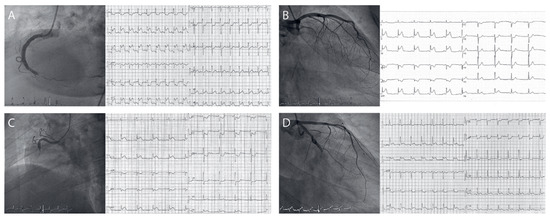

Reliability of an ECG-Algorithm for Identification of the Infarct-Related Artery in Inferior Myocardial Infarction in Clinical Practice

by Beate Buchmann, Tim Rönz and Piero O. Bonetti

Cardiovasc. Med. 2022, 25(1), 18; https://doi.org/10.4414/cvm.2022.02190 - 1 Jan 2022

BACKGROUND: The presence of ST-segment elevation in lead III exceeding that in lead II when combined with ST-segment depression in leads I, aVL or both, was proposed as a powerful predictor of occlusion of the right coronary artery with sensitivity/specificity values of 90%/71% in patients with acute inferior ST-segment elevation myocardial infarction (STEMI). The present study was performed to investigate the reliability of this ECG algorithm in clinical practice. METHODS: ECGs of all consecutive patients who presented to our hospital with acute inferior STEMI and underwent emergency coronary angiography / primary percutaneous coronary intervention between January 2006 and December 2013 were analysed retrospectively by two independent cardiologists according to the criteria mentioned above. The results were then compared with the angiographic findings and 28-day mortality data were collected. RESULT S: A total of 356 patients with acute inferior STEMI were included in the present study. The right coronary artery was the infarct-related artery in 272 (76.4%) patients and the left circumflex coronary artery in 76 (21.4%) patients, whereas inferior STEMI was caused by distal occlusion of a large left anterior descending coronary artery in 4 (1.1%) and of the Ramus intermedius in 4 (1.1%) patients. In our population the sensitivity/specificity values of the proposed ECG algorithm to correctly identify the right coronary artery were 78%/49%. There was a non-significant trend towards a higher 28-day mortality in patients with a positive ECG algorithm (3.5% vs 1.0%, p = 0.186). CONCLUSIONS: In the present study we could not reproduce the excellent diagnostic accuracy of an ECG algorithm for predicting the infarct-related artery in acute inferior STEMI reported in the literature. Thus, given its suboptimal diagnostic reliability and the lack of therapeutic consequences in patients with acute inferior STEMI and a clear indication for immediate reperfusion therapy, the clinical relevance of the proposed ECG algorithm is questionable. Full article

Show Figures

Figure 1